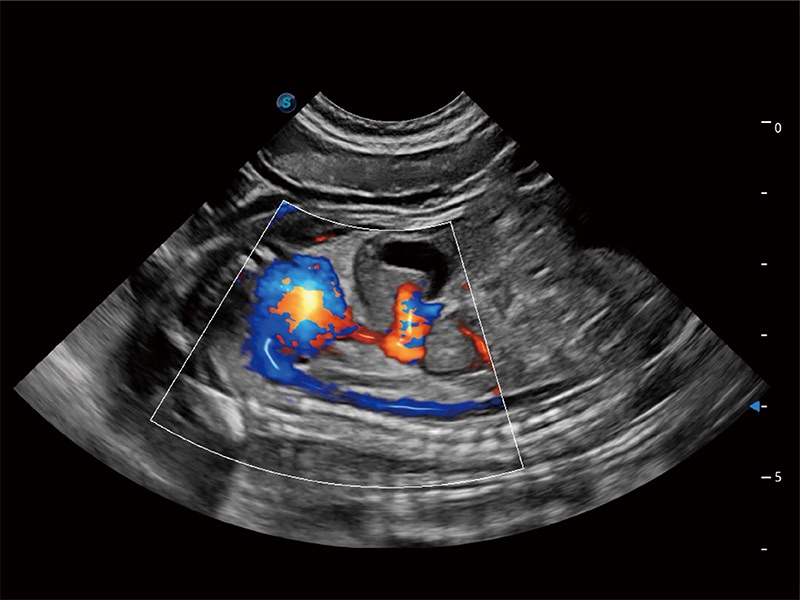

極大提升超低速微細血流的檢出能力,同時更精準地濾除軟組織和超聲信號,為獸用醫(yī)生提供以往無法通過常規(guī)血流獲得的疾病診斷信息。

在傳統(tǒng)二維血流成像的基礎(chǔ)上,呈現(xiàn)血流的立體感,具有動感的生命力之美。即便是微小的血管也能輕松應(yīng)對,提高了血流的視覺敏感性。